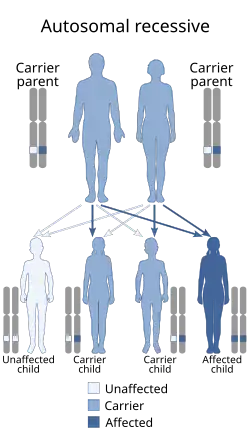

Spinal muscular atrophy is inherited in an autosomal recessive pattern, which means that the defective gene is located on an autosome. Two copies of the defective gene – one from each parent – are required to inherit the disorder: the parents may be carriers and not personally affected. SMA seems to appear de novo (i.e., without any hereditary causes) in around 2–4% of cases.

Spinal muscular atrophy affects individuals of all ethnic groups, unlike other well-known autosomal recessive disorders, such as sickle cell disease and cystic fibrosis, which have significant differences in occurrence rate among ethnic groups. The overall prevalence of SMA, of all types and across all ethnic groups, is in the range of 1 per 10,000 individuals; the gene frequency is around 1:100; therefore, approximately one in 50 persons are carriers.[26][27] There are no known health consequences of being a carrier. A person may learn carrier status only if one's child is affected by SMA or by having the SMN1 gene sequenced.